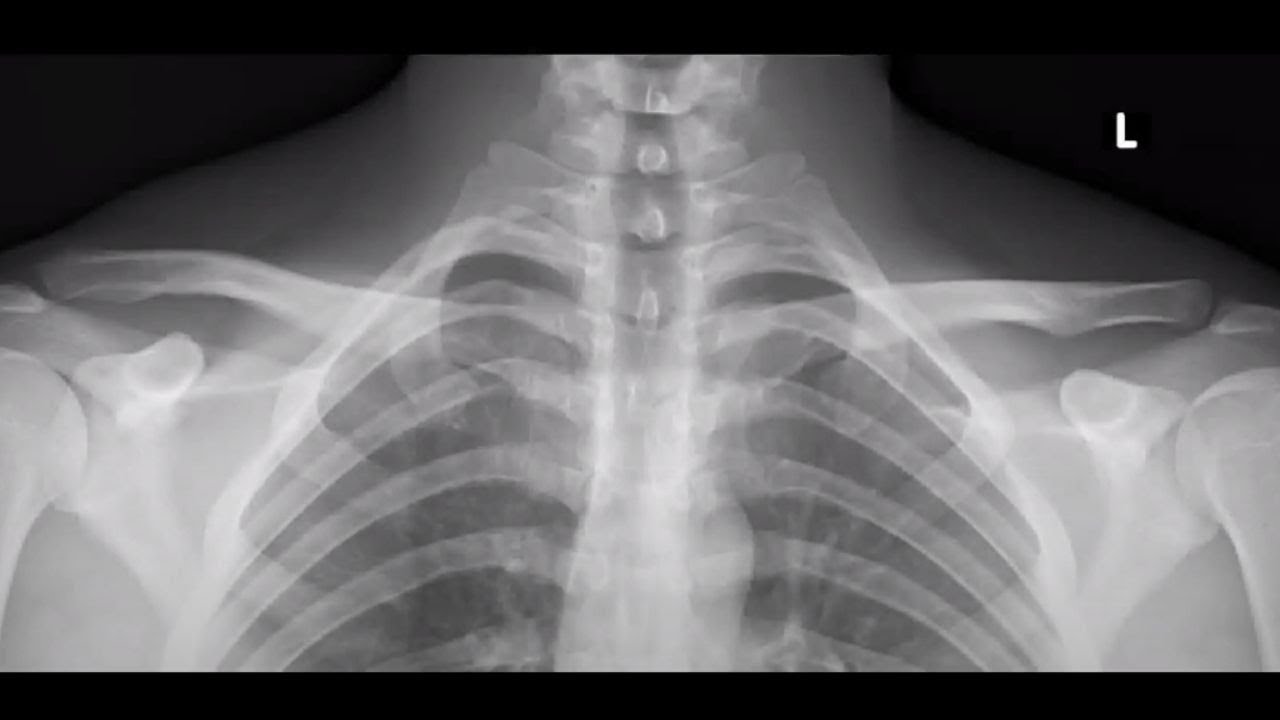

Рентгенография грудино-ключичных сочленений (со снимком)

Рентген грудино-ключичного сочленения назначают с целью диагностики заболеваний и травм, оценки динамики на фоне проводимого лечения.

На снимках визуализируется грудинный стержень, конец ключицы, суставное пространство. Рентген сочленения проводится амбулаторно, без контраста.